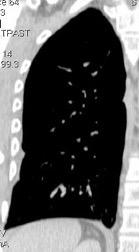

87. NEUMOTÓRAX ESPONTÁNEO

89. NEUMOTÓRAX. SÍNDROMES POROSOS

90. NEUMOTÓRAX A TENSIÓN

91. NEUMOTÓRAX EN ESPIRACIÓN

92. PLACAS PLEURALES